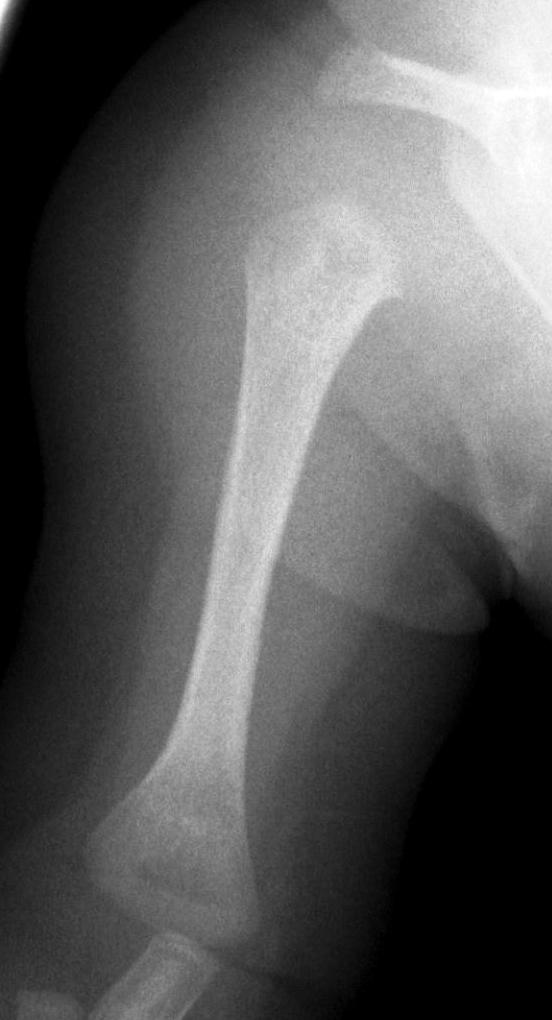

Image

37.a.

37.b.

37.c.

37.d.

37. a-d) X-ray of the right humerus. a. Rarefaction in the proximal-medial part of metaphysis of the right humerus – early osteomyelitis. b. Two weeks after the lytic area has grown. c. 1 month later sclerotic regeneration has begun. d. 4 months after almost complete healing. Osteomyelitis, infant.